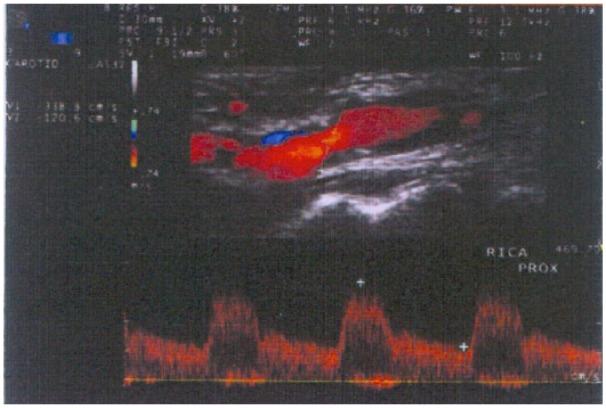

The third-generation thienopyridine prasugrel has much stronger antiplatelet effect compared to other current antiplatelet inhibitors and exhibits practically zero resistance in healthy people. Prasugrel is used as a pre- and post-treatment in percutaneous coronary or neurovascular interventions with parallel aspirin regime. However, as there is a higher reported bleeding with intraluminal interventions and meticulous technique is recommended, there is nearly non-existent international experience of open surgery under full prasugrel treatment. We present, herein, a case of open carotid endarterectomy with the eversion technique in an asymptomatic patient with carotid stenosis, who was receiving dual antiplatelet therapy with aspirin and prasugrel, due to a previous insertion of two newer drug-eluting stents at the left anterior descending artery and the right coronary artery. The resistance test to prasugrel showed complete inhibition of platelet function. Open surgery was performed under continuation of prasugrel treatment and interruption of aspirin for 3 days before surgery. No perioperative and postoperative neurologic or cardiologic event occurred. No bleeding at the cervical or cerebral area was noted.

与目前其他抗血小板抑制剂相比,第三代噻吩并吡啶类药物普拉格雷具有更强的抗血小板作用,在健康人群中几乎表现为零抵抗。普拉格雷在经皮冠状动脉或神经血管介入治疗前后使用,并与阿司匹林联合使用。然而,由于腔内介入治疗后出血的报道较多,建议采用精细技术,目前几乎没有在完全使用普拉格雷治疗下进行开放手术的国际经验。在此,我们报告一例无症状颈动脉狭窄患者,因先前在左前降支和右冠状动脉置入了两个新型药物洗脱支架,正在接受阿司匹林和普拉格雷双重抗血小板治疗,采用外翻技术进行了开放性颈动脉内膜切除术。对普拉格雷的抵抗试验显示血小板功能完全受到抑制。在继续使用普拉格雷治疗并在手术前3天停用阿司匹林的情况下进行了开放手术。围手术期和术后未发生神经或心脏事件。未发现颈部或脑部出血。